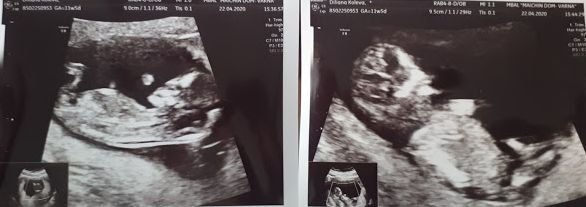

Хей, хей, днес май е бил денят на прегледите Simple Smile Идвам да ви поръся с почти 90% сигурен двоен син, смучеш си палците прашец 🧚‍♂️🧚‍♂️

И двамата  са добре, вече мърдат, ритат и приличат все повече на бебета Wink

п.с. за тези, които се радват на такива снимки, представям ви Б1 и Б2:

Дидииии Blue HeartBlue Heart

Излезе правилно усещането ти за момченца ! Blush

Ама те цели човечета вече, прекрасни !